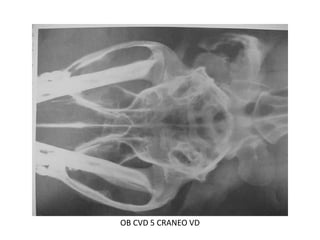

Posición Ventrodorsal

donde se observa, bulla

timpanica, boveda

craneana,senos nasales,

maxilar, parte de la

dentadura.

OB CVD 4 ventrodorsal craneo

OB CVD 5 CRANEO VD